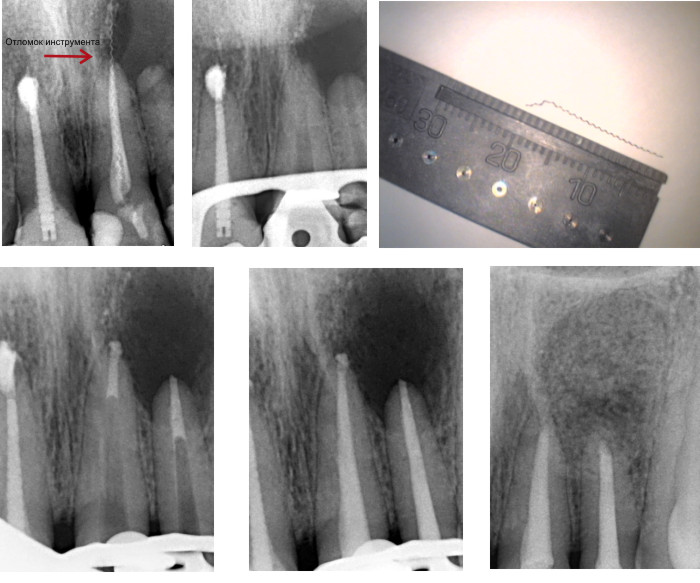

Пациент испытывал боль в области передних верхних зубов и до того, как обратиться к нам, посетил несколько клиник, где ему констатировали большую кисту в области двух передних верхних зубов и рекомендовали эти два зуба удалить вместе с кистой. Мы диагностировали наличие отломка инструмента в канале зуба, уходящего за верхушку корня и большую кисту в области двух верхних передних зубов. С помощью микроскопа был извлечен отломок инструмента и вылечены каналы без удаления зубов.